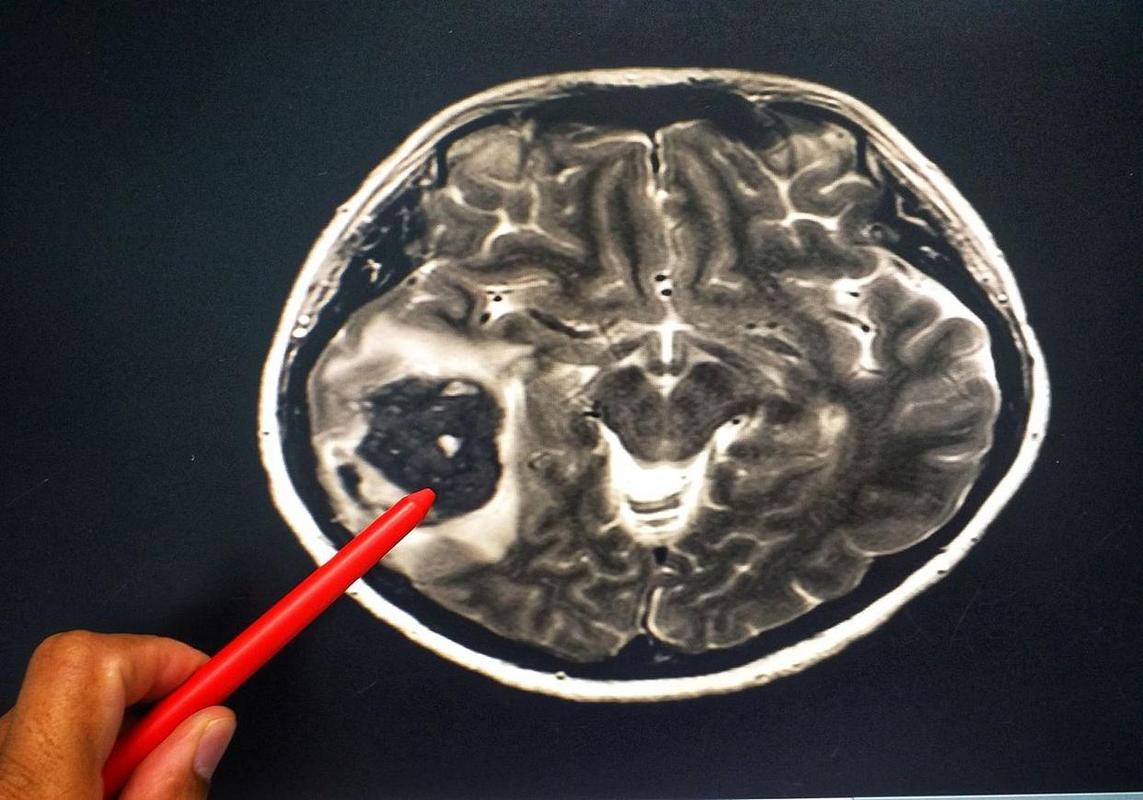

脑梗塞

- 俗称“中风”或“脑卒中”,是指因脑部血管阻塞(最常见),导致局部脑组织缺血、缺氧,进而发生坏死的一种疾病。

- 通俗理解:就像水管堵了,下游的土地就干涸了,脑梗就是脑血管“堵了”,导致负责特定功能的脑细胞死亡。

- 局灶性症状:症状取决于堵塞血管的位置和所供应的脑区,堵塞供应运动区的血管会导致偏瘫;堵塞语言区会导致失语。

- 不可逆损伤:坏死的脑细胞无法再生,会留下永久性的后遗症(如肢体无力、言语不清等)。